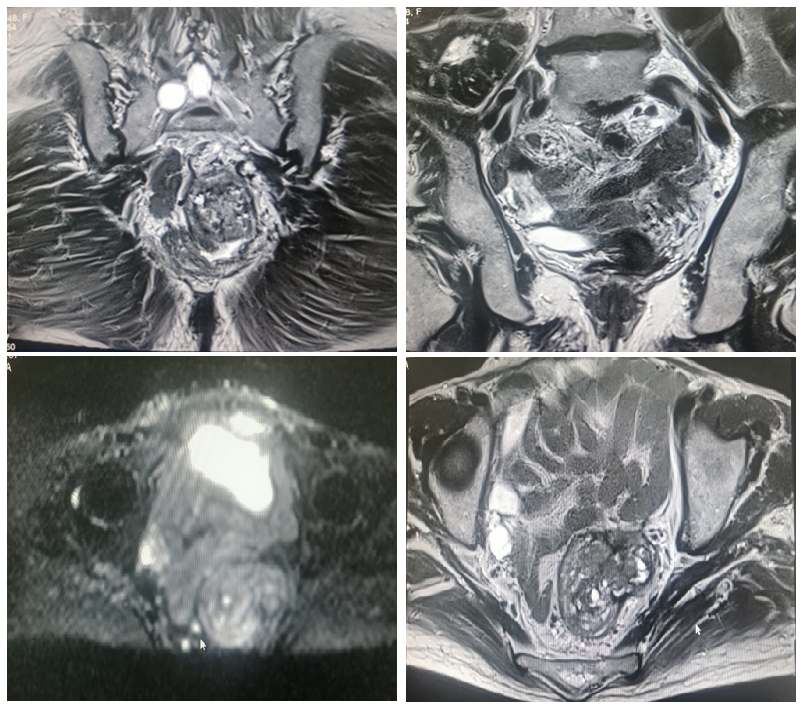

Squamous Cell Rectal Carcinoma: About A Rare and Unusual Case: A Case report

M. El Bouatmani, M. Michouar, A. Jallouli, A. Ait Errami, S. Oubaha, Z. Samlani, K. Krati, H. Rachidi, A. Belbachir